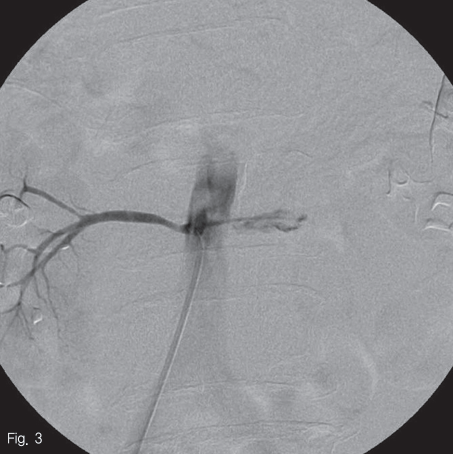

우측 대퇴동맥을 천자 후 5F straight catheter(Radifocus, Terumo, Tokyo, Japan)를 이용하여 시행한 대동맥 조영상 하부장간동맥 기시부 직하방에서 앞쪽으로 마제신의 양측 협부를 공급하는 좌,우 분지동맥이 공동동맥(common truck)을 이루고 있고 좌측 분지에서 현성 출혈로 판단되는 거짓동맥류가 있었다(Fig.2). 5F RH catheter(Cook, Bloomington, U.S.A)를 사용하여 공동동맥(common truck)를 선택하여 시행한 angiogram에서 좌측 분지에서 기원하는 거짓동맥류를 확인하였다(Fig.3).

Fig 3

Selective common trunk arteriogram showed contrast filling sac(arrow) from left side branch.